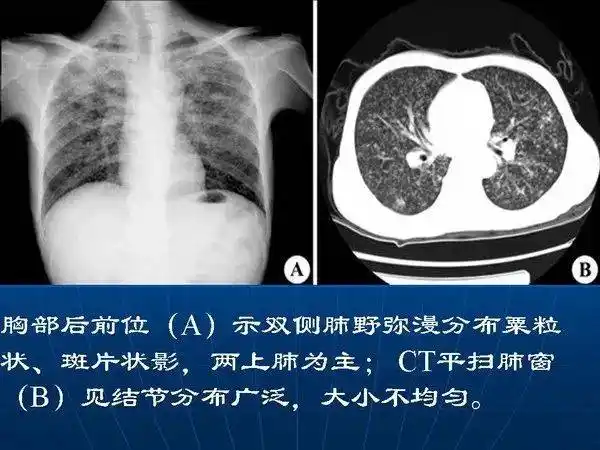

各型肺结核的典型影像表现